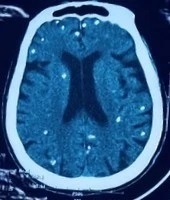

Nhiều nốt cản quang trong nhu mô não của người bệnh. Ảnh: BVCC.

Giai đoạn không nang: Trên CT hoặc MRI chưa thấy nang rõ, chỉ có vùng phù nhẹ. Sau vài tháng, phôi phát triển thành nang đặc trưng.

- Giai đoạn nang dịch: Nang có thành mỏng, chứa dịch trong và ký sinh trùng bên trong. Nếu còn nguyên vẹn, người bệnh có thể chưa có triệu chứng.

- Giai đoạn nang keo: Thành nang dày, dịch bên trong đục. Phản ứng viêm mạnh xuất hiện, người bệnh dễ co giật.

- Giai đoạn nang hạt: Phù nề giảm dần nhưng động kinh vẫn có thể xảy ra do phản ứng viêm quanh ký sinh trùng sắp chết.

- Giai đoạn canxi hóa: Xảy ra khi ký sinh trùng đã chết. Các cơn động kinh vẫn có thể tái phát do phản ứng miễn dịch với xác ký sinh trùng.